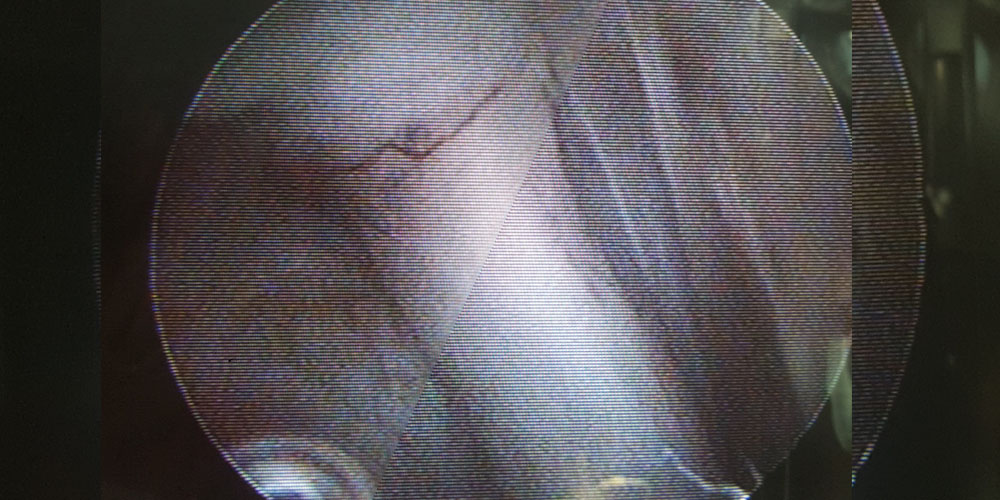

Minimal invasive Chirurgie (MIC)

Mit der Minimal invasiven Chirurgie nutzen wir kleinstmögliche Zugänge zu den Körperhöhlen Ihres Tieres. Die Laparoskopie im Bauchraum, die Thorakoskopie im Brustraum, stellen neue chirurgische Techniken dar, die insgesamt das Trauma einer Untersuchung oder Operation gegenüber herkömmlichen Schnitten deutlich verringern. Durch die hier sehr klein angelegten Schnitte werden starre Endoskope mit angeschlossener Videokamera, Lichtquelle und chirurgische Instrumente in die Körperhöhle eingebracht um die Operation im Inneren der Körperhöhle unter Videosicht durchzuführen. Wir führen diagnostisch Biopsien der inneren Organe Leber, Niere, Bauchspeichdrüse, Prostata und Zubildungen durch, operativ die endoskopische Kastration, Sterilisation, Kryptorchiden Kastration und Gastropexie.

Die Vorteile der minimal invasiven Chirurgie sind die kleineren Einschnitte mit geringerer Narbenbildung, der deutlich reduzierte post operative Wundschmerz, sowie die raschere Mobilisierung und mögliche Rückkehr zur normalen Aktivität Ihres Tieres.